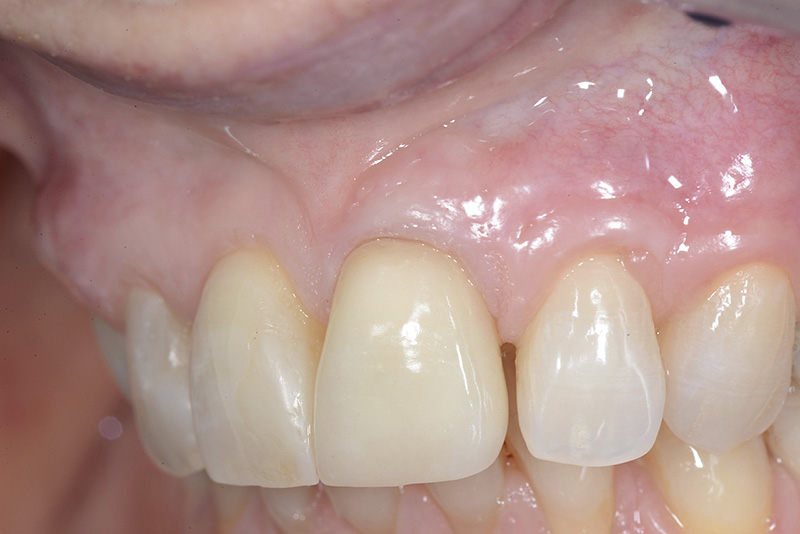

PREMESSA: in seguito all’estrazione dell’incisivo laterale superiore di destra, resasi necessaria per cause batteriche, si decide di affrontare il caso con il posizionamento di un impianto in sostituzione dell’elemento mancante dopo guarigione del sito infetto. Con tecniche rigenerative sia dei tessuti ossei mancanti a causa dell’infezione pregressa, sia dei tessuti gengivali che appaiono inizialmente troppo spostati in alto, si ripristina una corretta morfologia delle parabole (contorni) gengivali e delle papille interdentali (triangoli di gengiva tra due denti vicini).

Vengono utilizzati 2 tipi di provvisori: il primo, cementato ai denti vicini, viene utilizzato dal momento dell’estrazione del dente fino ad impianto osteointegrato (circa 6 mesi); il secondo, avvitato direttamente all’impianto, ha una funzione di prova estetica ma soprattutto di guida per la maturazione dei tessuti gengivali peri-implantari portandoli verso la maturazione completa prima di posizionare la corona finale in disilicato di litio.